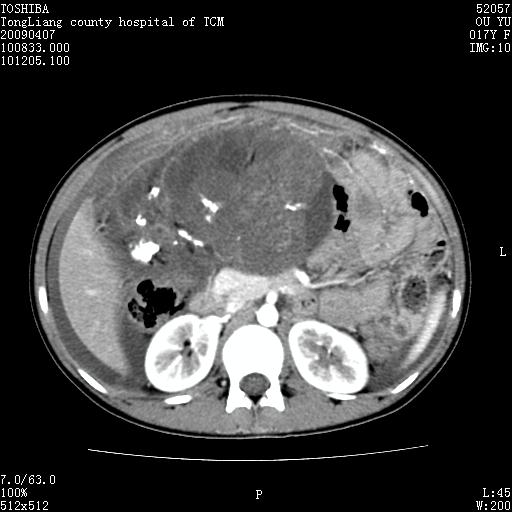

女,17岁,腹胀1月,b超示腹腔内巨大占位病变,腹水;

ct示腹腔内不均匀软组织肿块影,可见多数钙化灶(ct值400--800).周围肠管推移.

增强后,肿块内软组织不均匀强化,病灶内钙化灶边缘可见脂肪密度,肿块有包膜.向下与达盆腔.

腹部巨大紊杂密度肿块,边界不清楚,内有密度不均的软组织,多发不均匀钙化,钙化周围可见脂肪密度影,腹腔内可见积液及肿块内亦见液密密度区.增强后肿块内实质部分不均匀强化.钙化灶边缘脂肪灶显示更清楚.肠腔明显受推移.考虑畸恶性胎瘤.